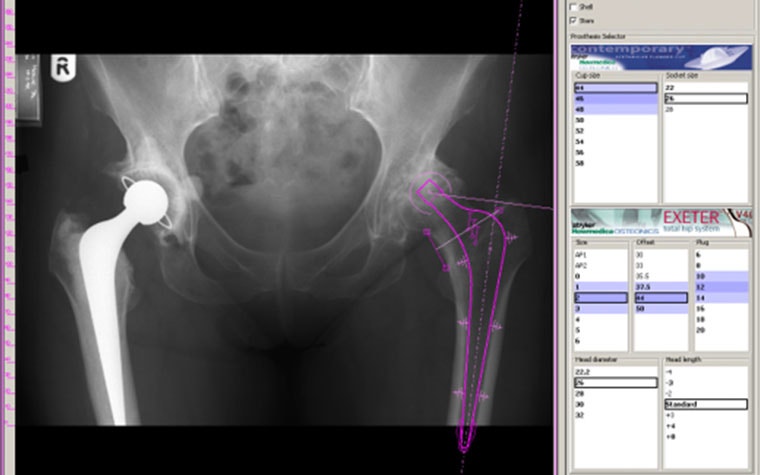

The way surgeons had to conduct preoperational planning before PACS and OrthoView (left) and a view of the software used for hip implant planning in 2003 (right).

An example is with acetate templating. "You try your best to find one that matches your image's size, then move it around on your X-ray," says Dr. Shaw. He continues, "You look at the offset and the component size and do a bit of fine-tuning. And when you think it's in the right place, stick it on with a bit of tape." The digital world presented an opportunity to improve on this.

So, the team came up with smart templates, which give surgeons the landmarks to position templates in almost the right place with just a few clicks. Dr. Shaw adds, "Particularly what’s good is the fact that there's a bit of intelligence built in them, so they know prompts like screws and parts moving together rather than the surgeon physically moving each part." Dave explains, "The intelligence was built in right from the beginning because we knew how useful it would be." The team's dedication led to discoveries that formed today's automation and is something that is still being improved upon every year.

Connected to template positioning was automatic scaling. Standard X-rays are a problem because each one is slightly different, and they're not all on the same scale. When surgeons were doing acetate templating, they were made at something like 120%, which roughly matched the average magnification but depended on the patient's size. Using acetates, surgeons had to hold up different sizes until they found one that fit. Dr. Shaw adds, "We just had to accept that the traditional templating was a bit inaccurate on occasions."

Digitally, surgeons can ask the software to recognize the required scale automatically. "The templates scale to the X-ray correctly, which considerably improves the accuracy of the template. The biggest advantage is that the planning will match the final result," explains Dr. Shaw.